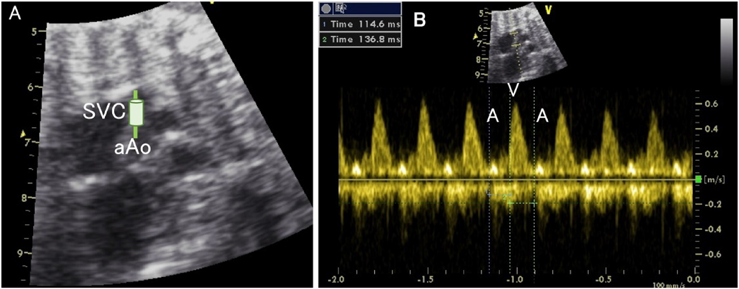

The pattern of the venous blood flow waveform is an index of circulatory failure (Fig. 17). The P wave of the electrocardiogram corresponds to the phase when the ventricles approach the end of diastole (the end-diastolic phase) and when the atria contract to pump blood out to the ventricles during the cardiac cycle.

Some atrial blood flows back from the atria into the venous system (a retrograde fraction) up to the end-diastolic pressure of the ventricle. By evaluating whether a retrograde flow is present and how significant the retrograde blood flow is, the central venous pressure is estimated. Increased central venous pressure is an index of heart failure.

Retrograde blood flow during atrial contraction is observed in the venous vessels close to the heart (such as the inferior vena cava) even under the normal circumstance. This effect related to atrial contraction becomes much less at the venous lumen distant from the heart. The blood flow in the distal umbilical vein is steady in a normal instance.65–70)

2. The preload index of the inferior vena cava at the right atrium is a ratio of the reflux velocity during atrial systole to the inflow velocity during ventricular systole. The ratio ≥0.5 is abnormal. (Fig. 18)71–73)

A notch is observed concomitantly with the P wave in the normal ductus venosus. A notch deeper than normal together with a retrograde flow is regarded as abnormal.74–77) In the umbilical vein, the flow velocity decreases as the venous pressure increases, resulting in a notch during the cardiac phase that coincides with atrial contraction; this makes the umbilical vein pulsatile.78–80) The waveform in the umbilical vein is a marker of placental function and the severity of fetal growth restriction.81, 82)